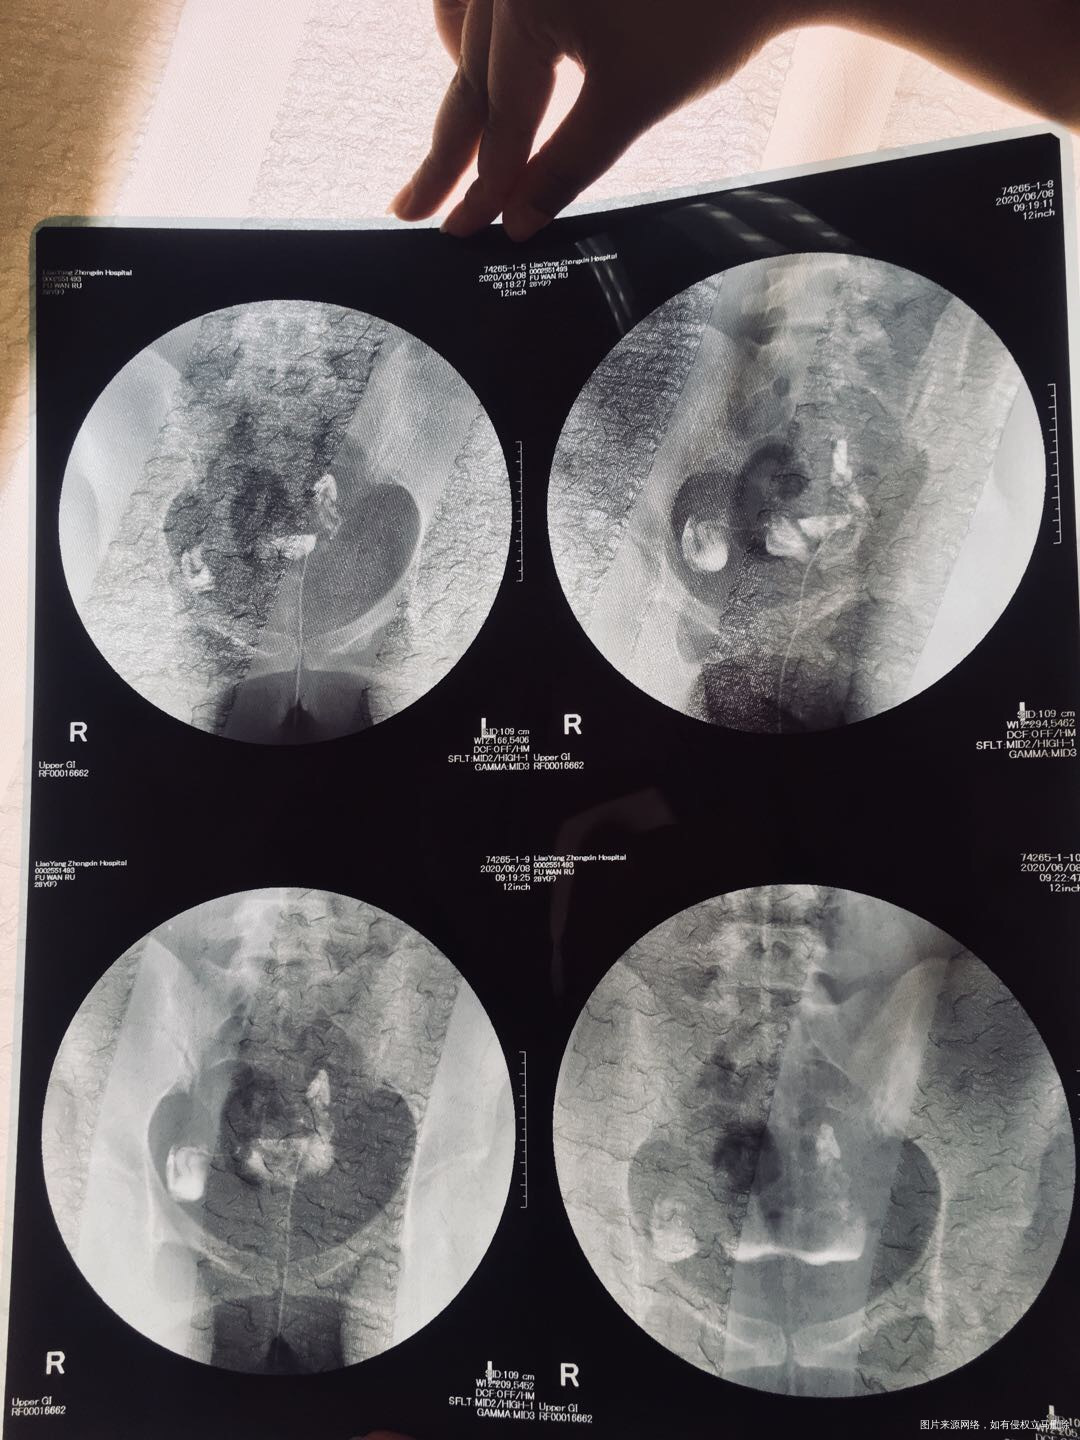

两年未怀孕,没做过手术,也没怀过孕,2020年6月8号做输卵管造影,显示一侧通畅一侧积水,隔天10号做了通液,未通开,中药灌肠20天,又促排3月未怀孕